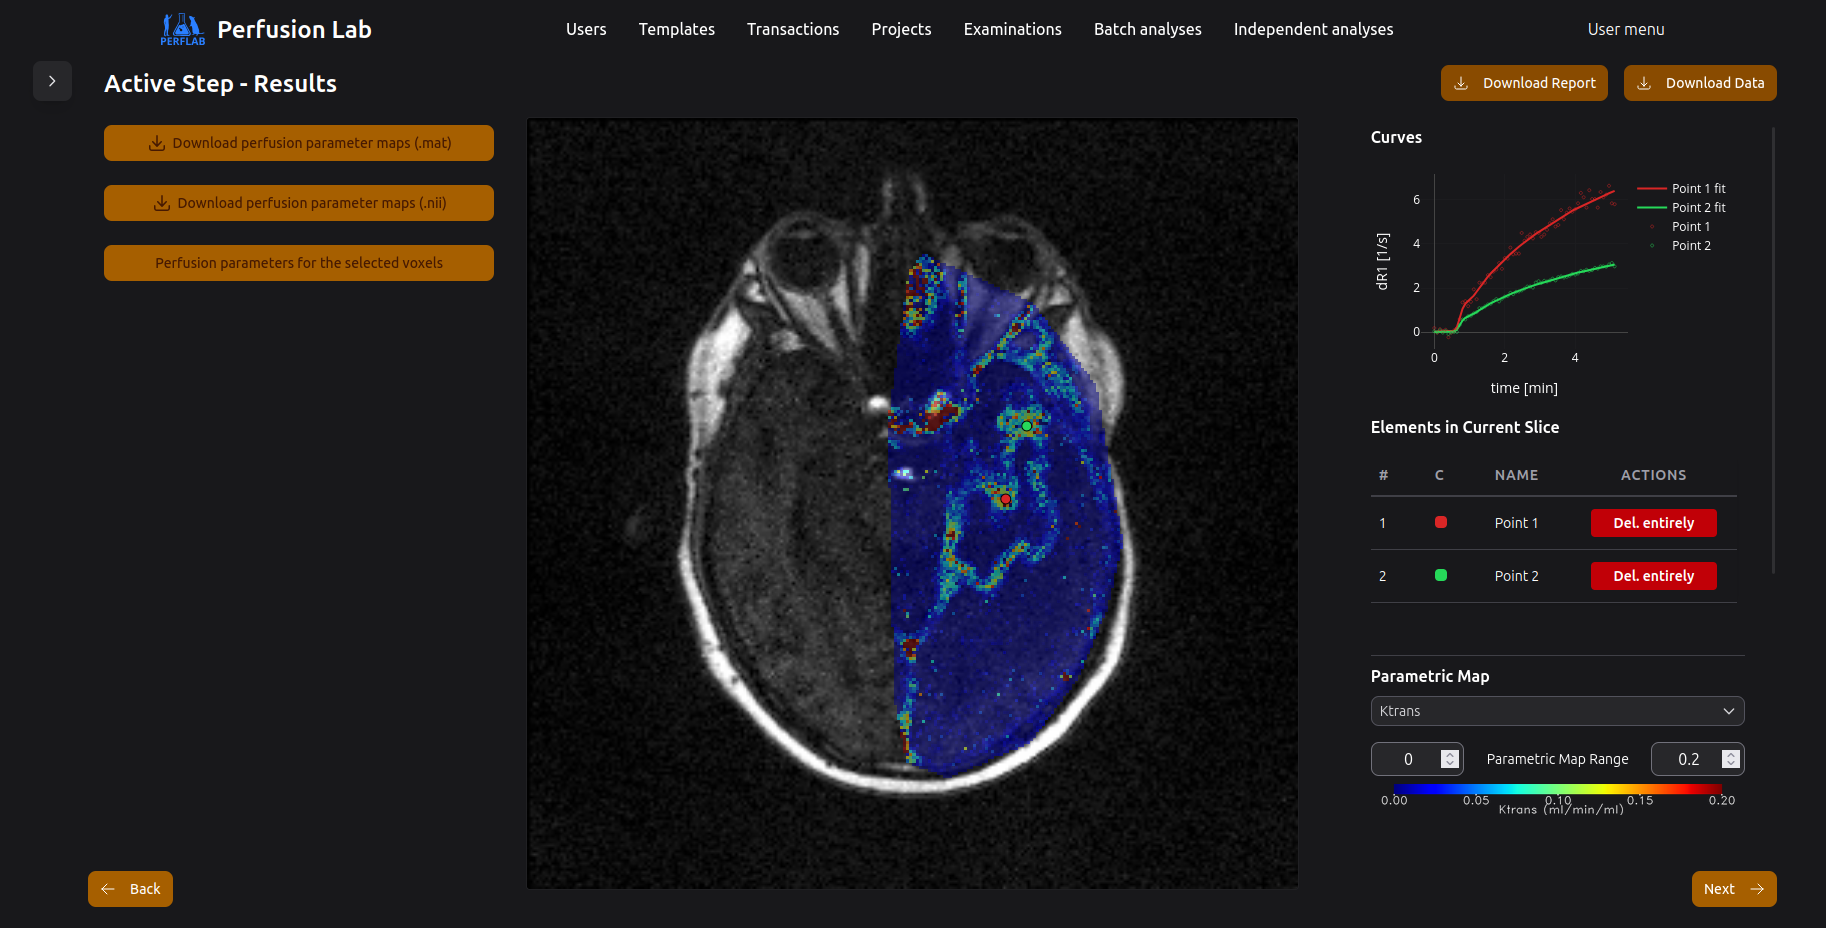

Read more →We offer processing of MR data measured at our core facility or elsewhere.

Read more →Development of software and graphical interferences for processing of MRI data